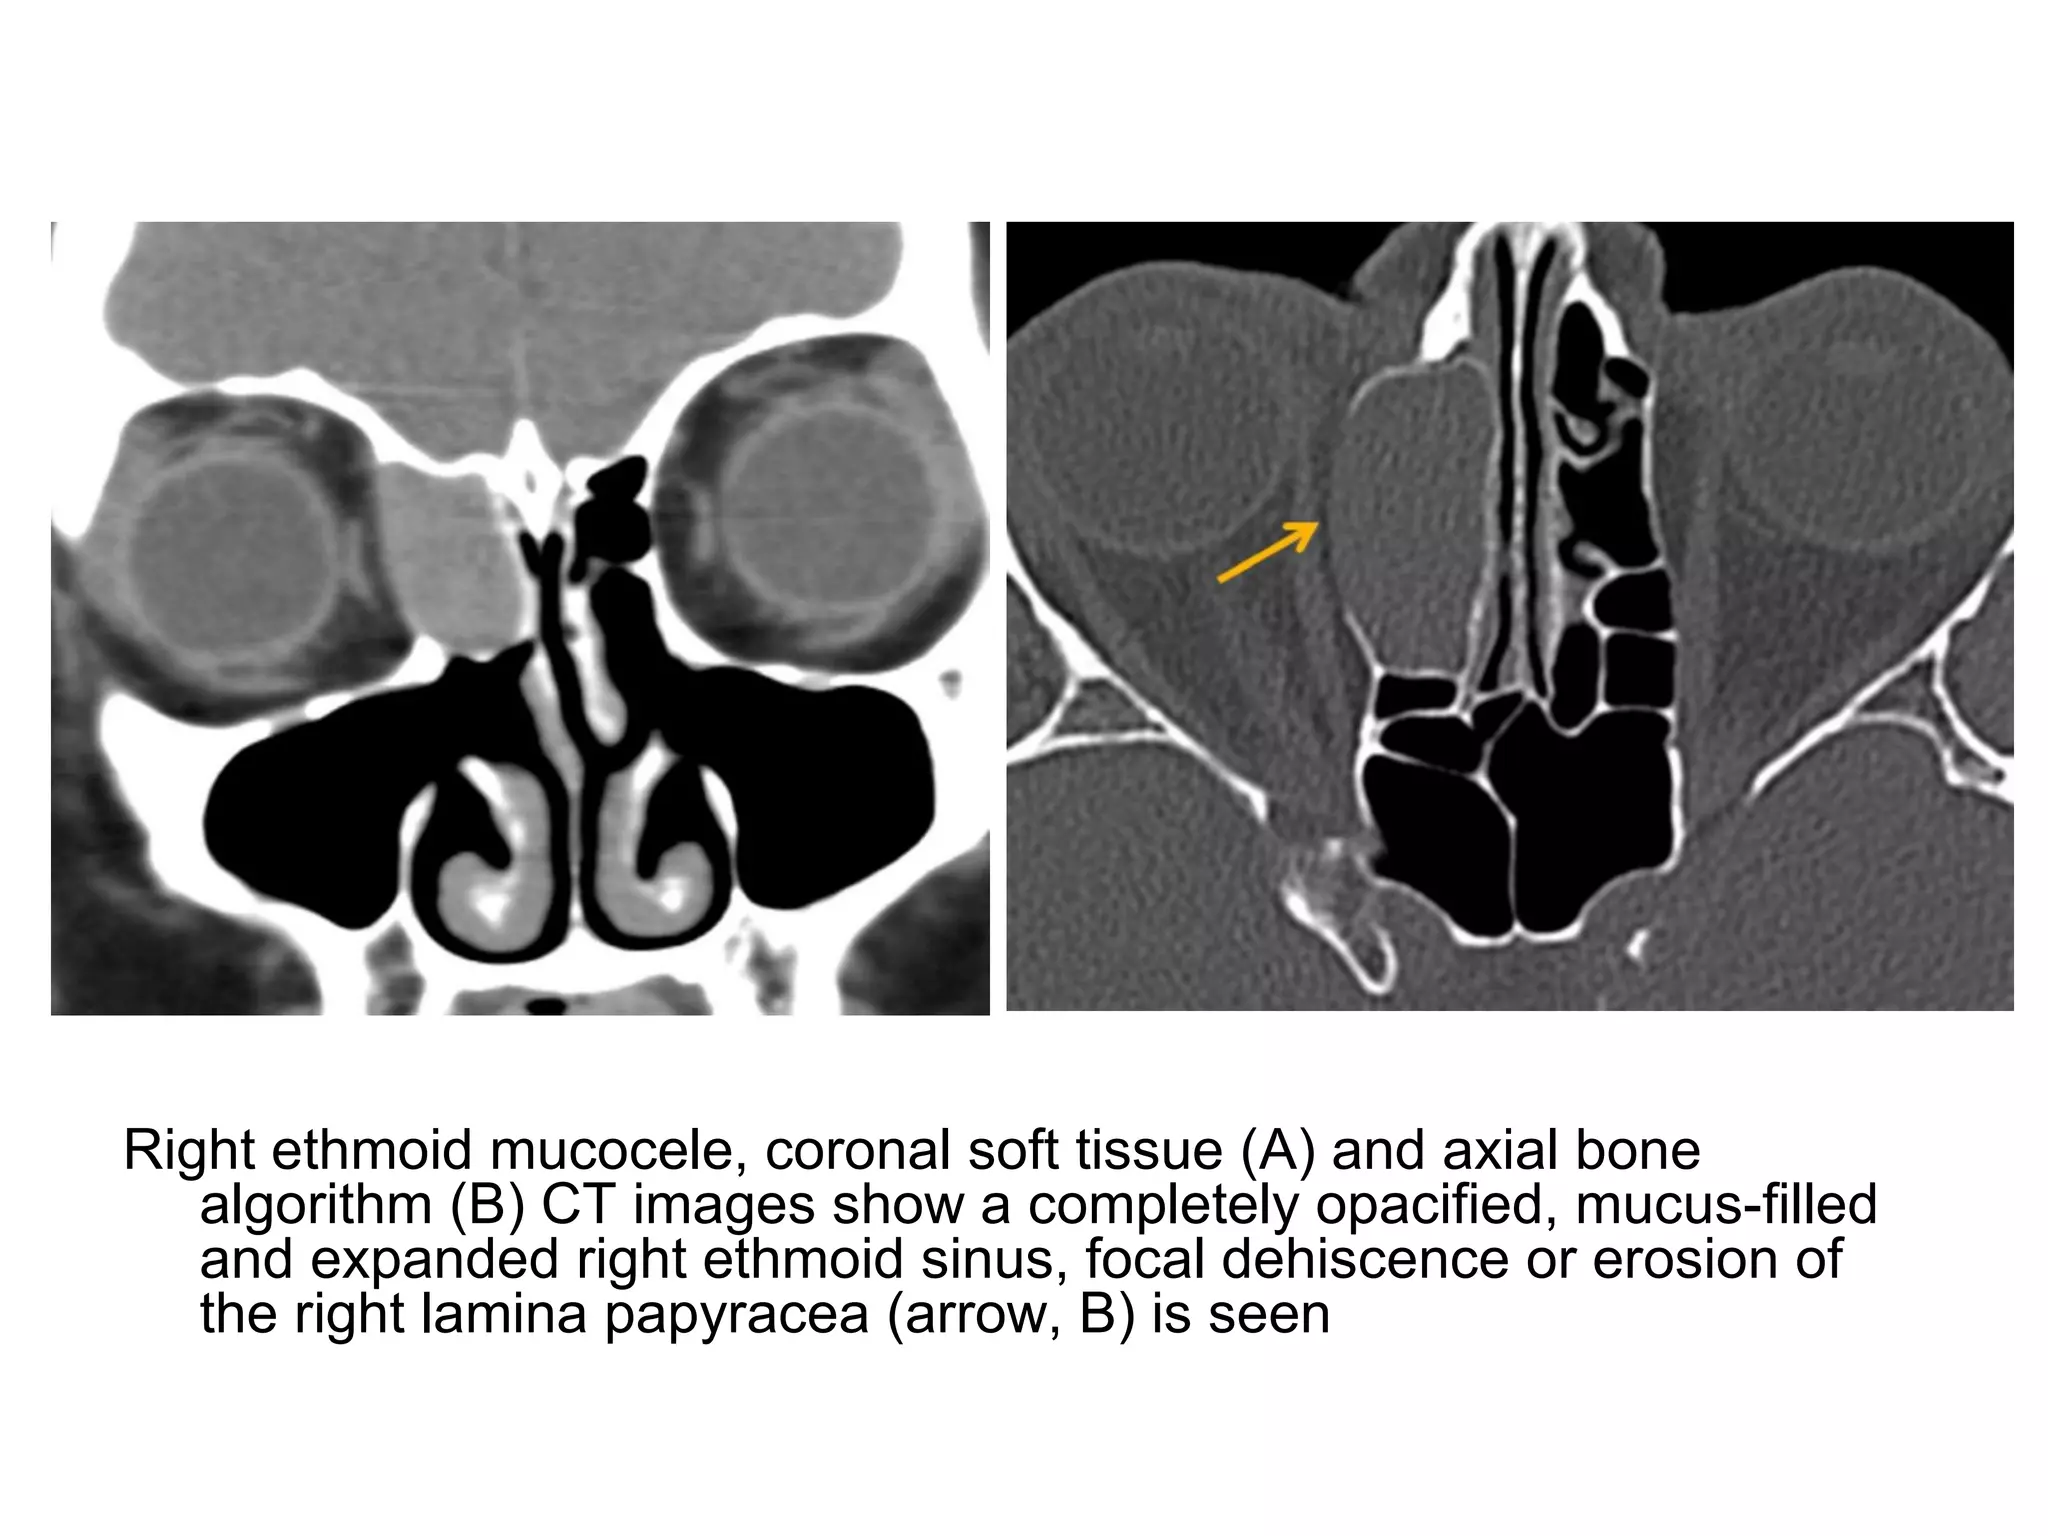

Right ethmoid mucocele, coronal soft tissue (A) and axial bone

algorithm (B) CT images show a completely opacified, mucus-filled

and expanded right ethmoid sinus, focal dehiscence or erosion of

the right lamina papyracea (arrow, B) is seen